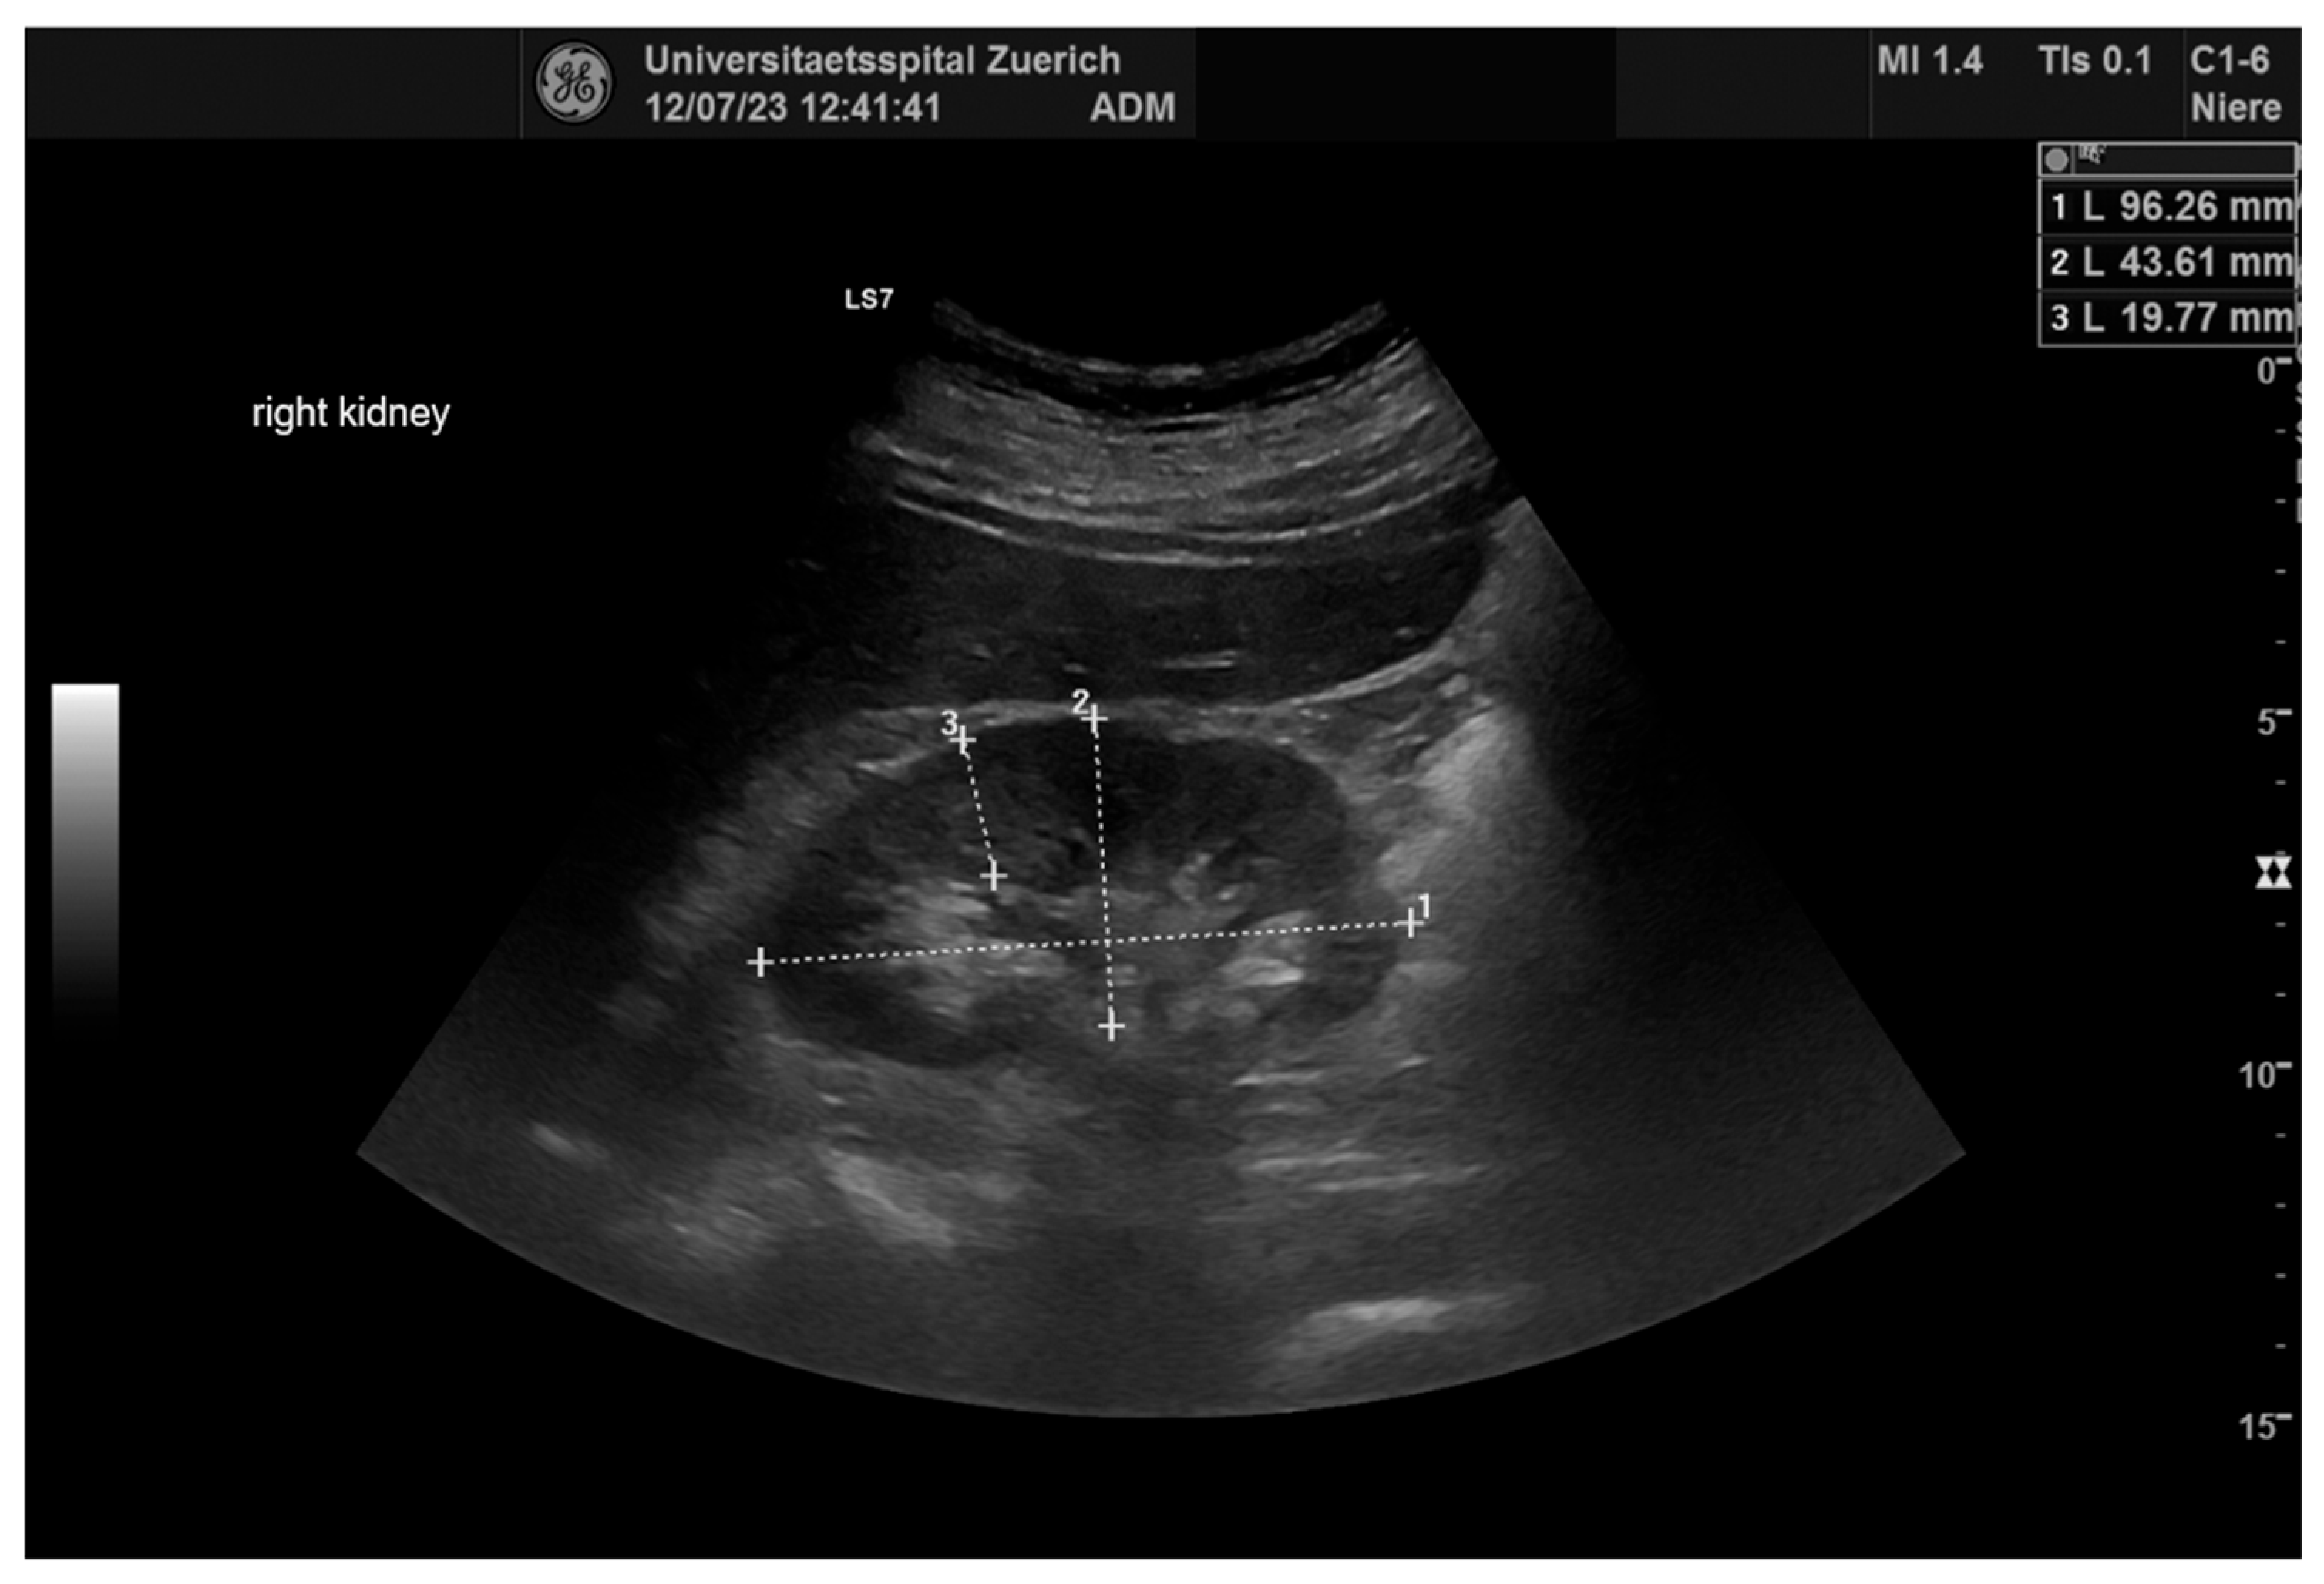

2.4. Ultrasonography

| Renal Parameters (n = 64) | Pre-Operative | Post-Operative | p |

| RRI | 0.66 ± 0.06 | 0.67 ± 0.07 | ns |

| Length (mm) | 107.1± 13.8 | 107.9 ± 14.5 | ns |

| Wide (mm) | 52.4± 7.9 | 52.9 ± 7.8 | ns |

| Parenchymal margin (mm) | 18.3 ± 3.2 | 18.6 ± 2.8 | ns |